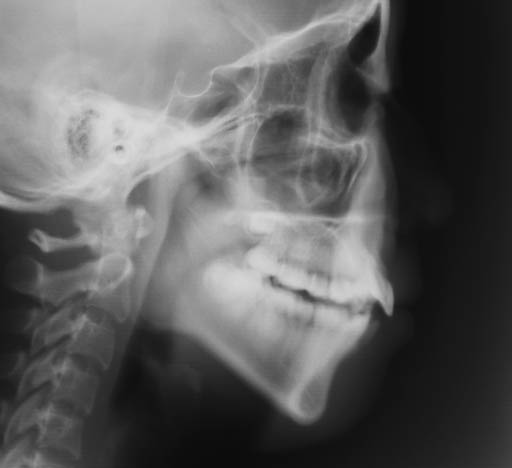

| セファロ所見 | 骨格的にはANB5.1°と前後的な不調和が認められ、 FMAが37.5°とハイアングルを呈していた。U1 to A-Pogが13.3mm、L1 to A-Pogが17.1mmと突出していた。 |